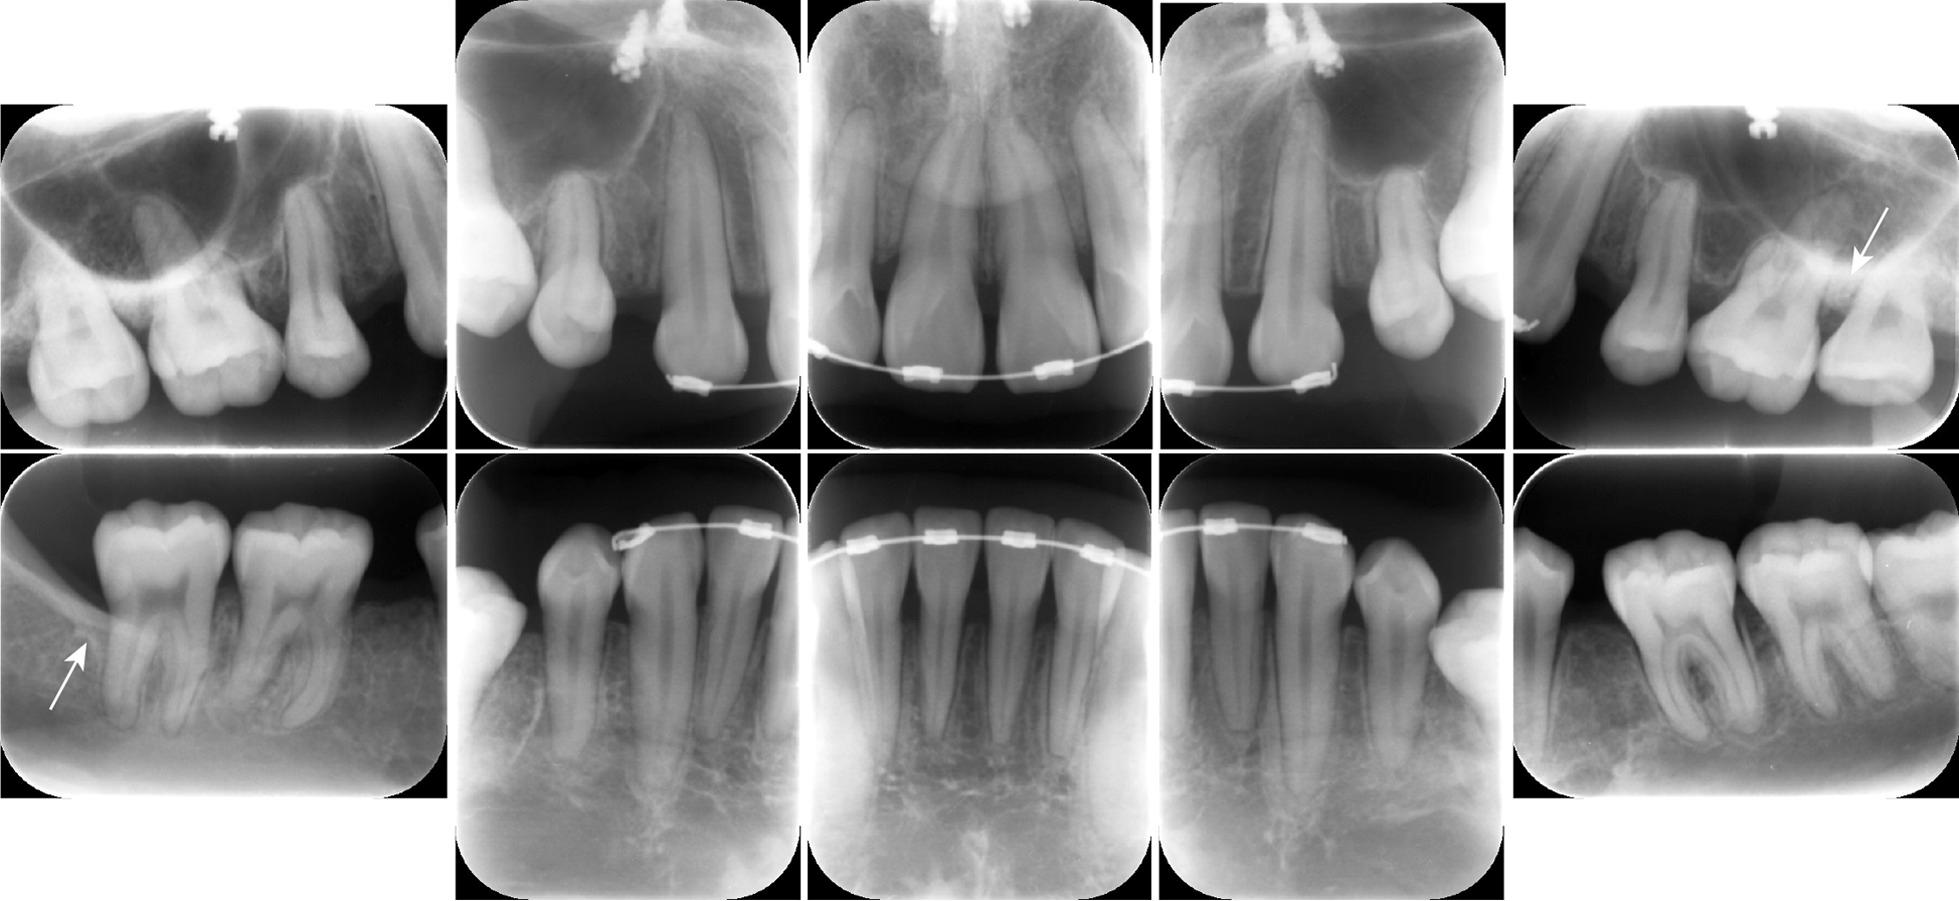

A 32-year-old Japanese woman was referred to the Department of Dentistry and Oral Surgery by an orthodontist who observed symptoms of acute periodontitis in the maxillary molars that required periodontal examination and treatment. A detailed periodontal examination, including oral bacteriological examination, revealed localized severe periodontitis (stage III, grade B) in the maxillary left first and second molars and in the mandibular right second molar. After consultation with the orthodontist, the orthodontic treatment was suspended based on the results of the bacteriological examination to allow for periodontal treatment. Full-mouth disinfection was performed with adjunctive oral sitafloxacin. Periodontal and bacteriological examinations after treatment revealed regression of the localized periodontitis with bone regeneration. Thereafter, orthodontic treatment was resumed, and good progress was achieved.

一名 32 岁的日本女性因正畸医生观察到上颌磨牙有急性牙周炎的症状而被转介到口腔科。详细的牙周检查,包括口腔细菌学检查,发现上颌左侧第一和第二磨牙以及下颌右侧第二磨牙存在局限性严重牙周炎(III 期,B 级)。根据细菌学检查结果,在与正畸医生协商后,暂停正畸治疗以进行牙周治疗。全口消毒采用辅助口服司他沙星。治疗后的牙周和细菌学检查显示,局部牙周炎有消退和骨再生。此后,恢复正畸治疗,取得了良好的进展。